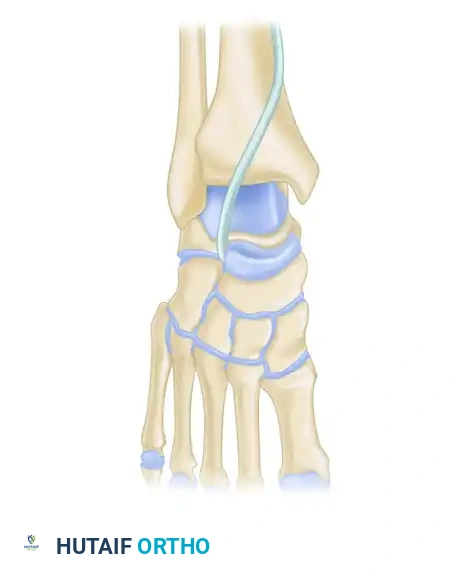

Subtalar dislocations, accurately termed peritalar dislocations, represent a severe and complex disruption of the hindfoot architecture. In this injury pattern, the calcaneus, cuboid, navicular, and the entire forefoot become simultaneously displaced from the talus. The tibiotalar and calcaneocuboid articulations typically remain intact, while the talocalcaneal (subtalar) and talonavicular joints are completely dislocated.

Subtalar dislocations are classified based on the direction of the distal foot segment relative to the talus.

Medial dislocations are the most common, comprising approximately 80% of all peritalar dislocations. The mechanism of injury is typically a severe inversion force applied to a plantarflexed foot. The sustentaculum tali acts as a fulcrum, levering the talus out of its anatomic position.

Clinically, the foot presents in an acquired clubfoot posture—supinated and medially displaced. The head of the talus becomes highly prominent dorsolaterally, and the skin over the talar head is frequently blanched and under extreme tension.